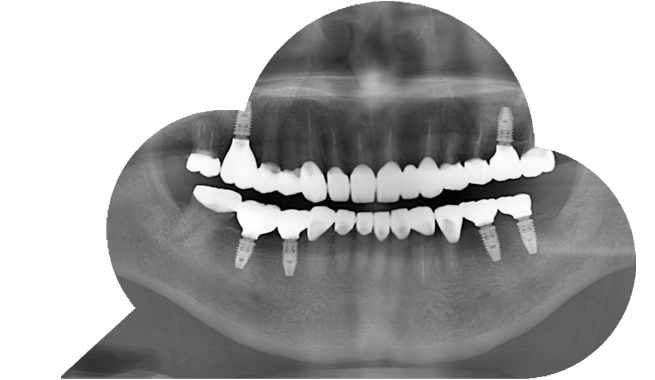

インプラント症例

57歳女性

治療前